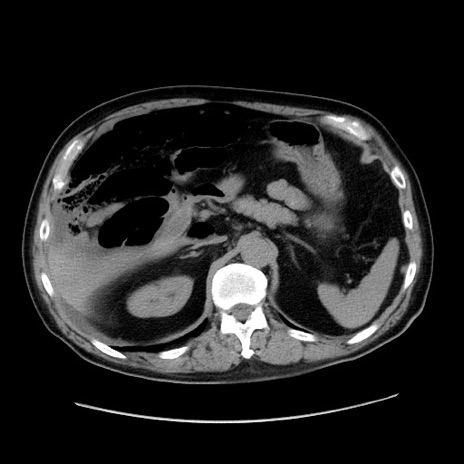

症例30(横断像)

【症例】80歳代男性

【主訴】臍周囲痛

【現病歴】約6時間前から臍下部痛が出現。次第に腹部膨隆・背部痛も生じてきたため来院。背部痛の場所は変化しない。

【身体所見】意識清明、BT 36.3℃、BP  131/87mmHg、P 87bpm、SpO2 100%(RA)、臍周囲自発痛・圧痛あり、反跳痛なし、自発痛部位に一致して板状硬あり、腹部膨隆、腸雑音減弱、CVA tenderness両側陰性。

【データ】WBC 19600、CRP 0.33

冠状断像